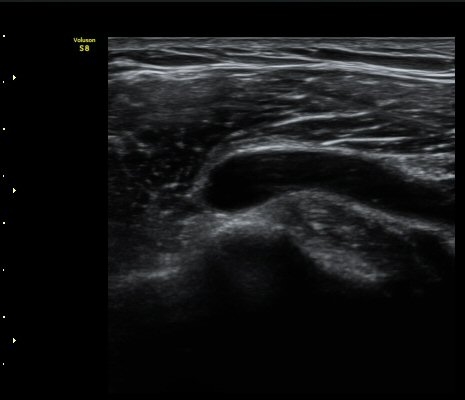

2049205267_d4912430_US181205109.jpg

2049205267_a5fe3a8a_US181253111.jpg

2049205267_e81a53aa_US181338113.jpg